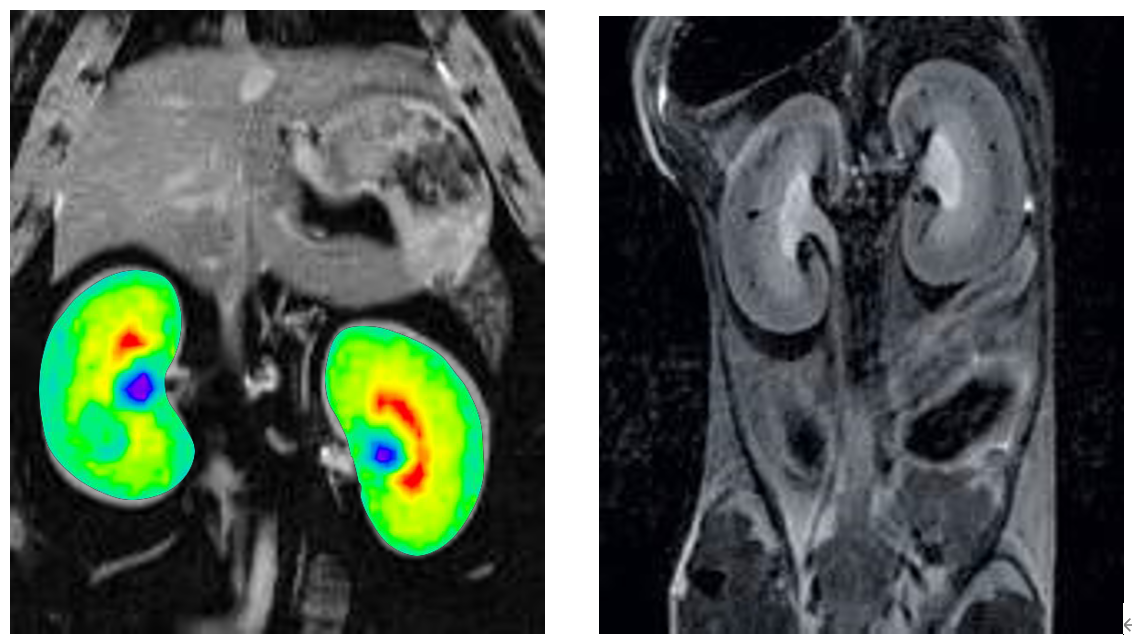

6、腹部成像

布魯克同步觸發(fā)采集技術(shù)可以消除腹部運(yùn)動偽影,高場下T2對比度能更好顯示腹部各個臟器。

大小鼠腹部成像: